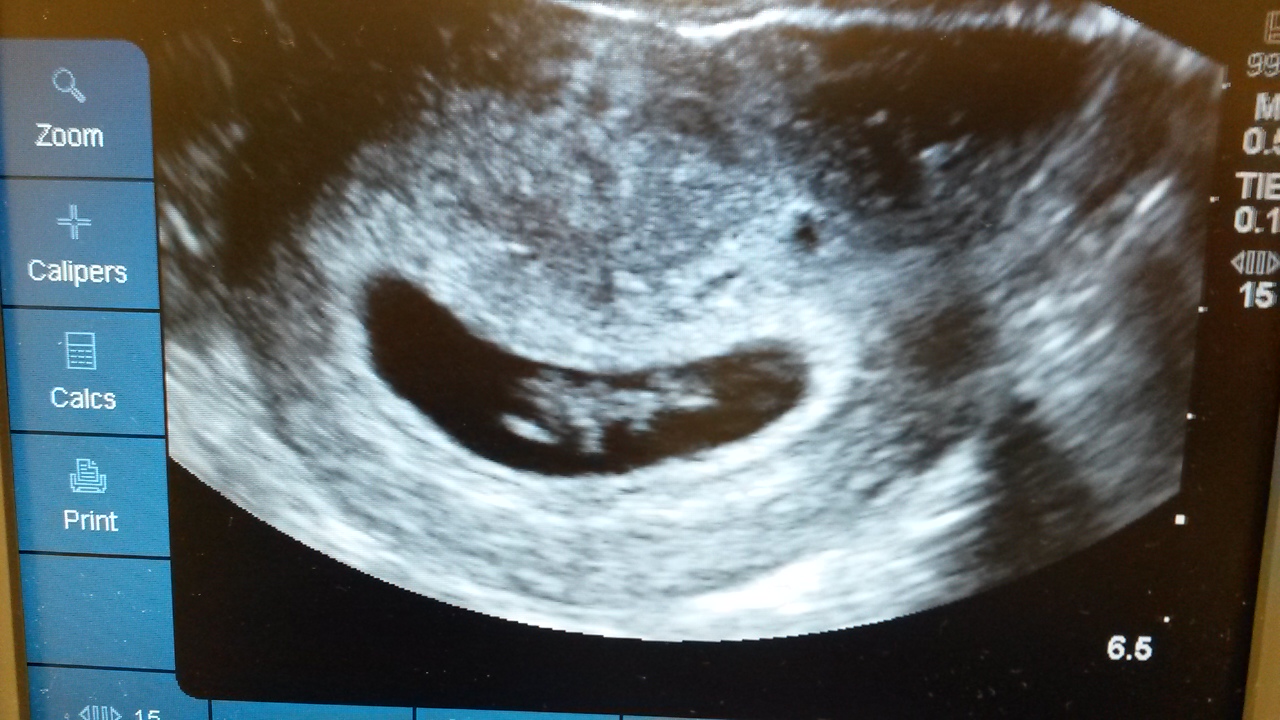

Got to see my little bean and the heartbeat today. Doc says I'm measuring 8w4d. According to LMP I'm 8w3d. Seeing that little flicker was the most surreal thing I've ever experienced! After my near accident yesterday this was such a relief. So happy that it's finally real for me. EDD was 10/4. Here's my little bean. Looks just like me!